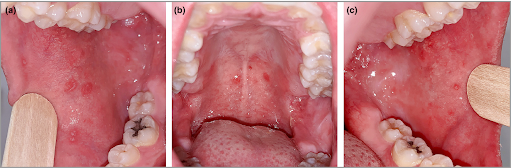

Gambar 2. Bercak putih kecil di dalam mulut (Koplik’s spot)

- Fase awal (prodromal)

Pada fase ini anak biasanya mengalami:- Demam tinggi (≥38°C) selama beberapa hari

- 3C: Batuk (Cough), pilek (Coryza), mata merah (Conjunctivitis)

- Bercak putih kecil di dalam mulut (Koplik spot)